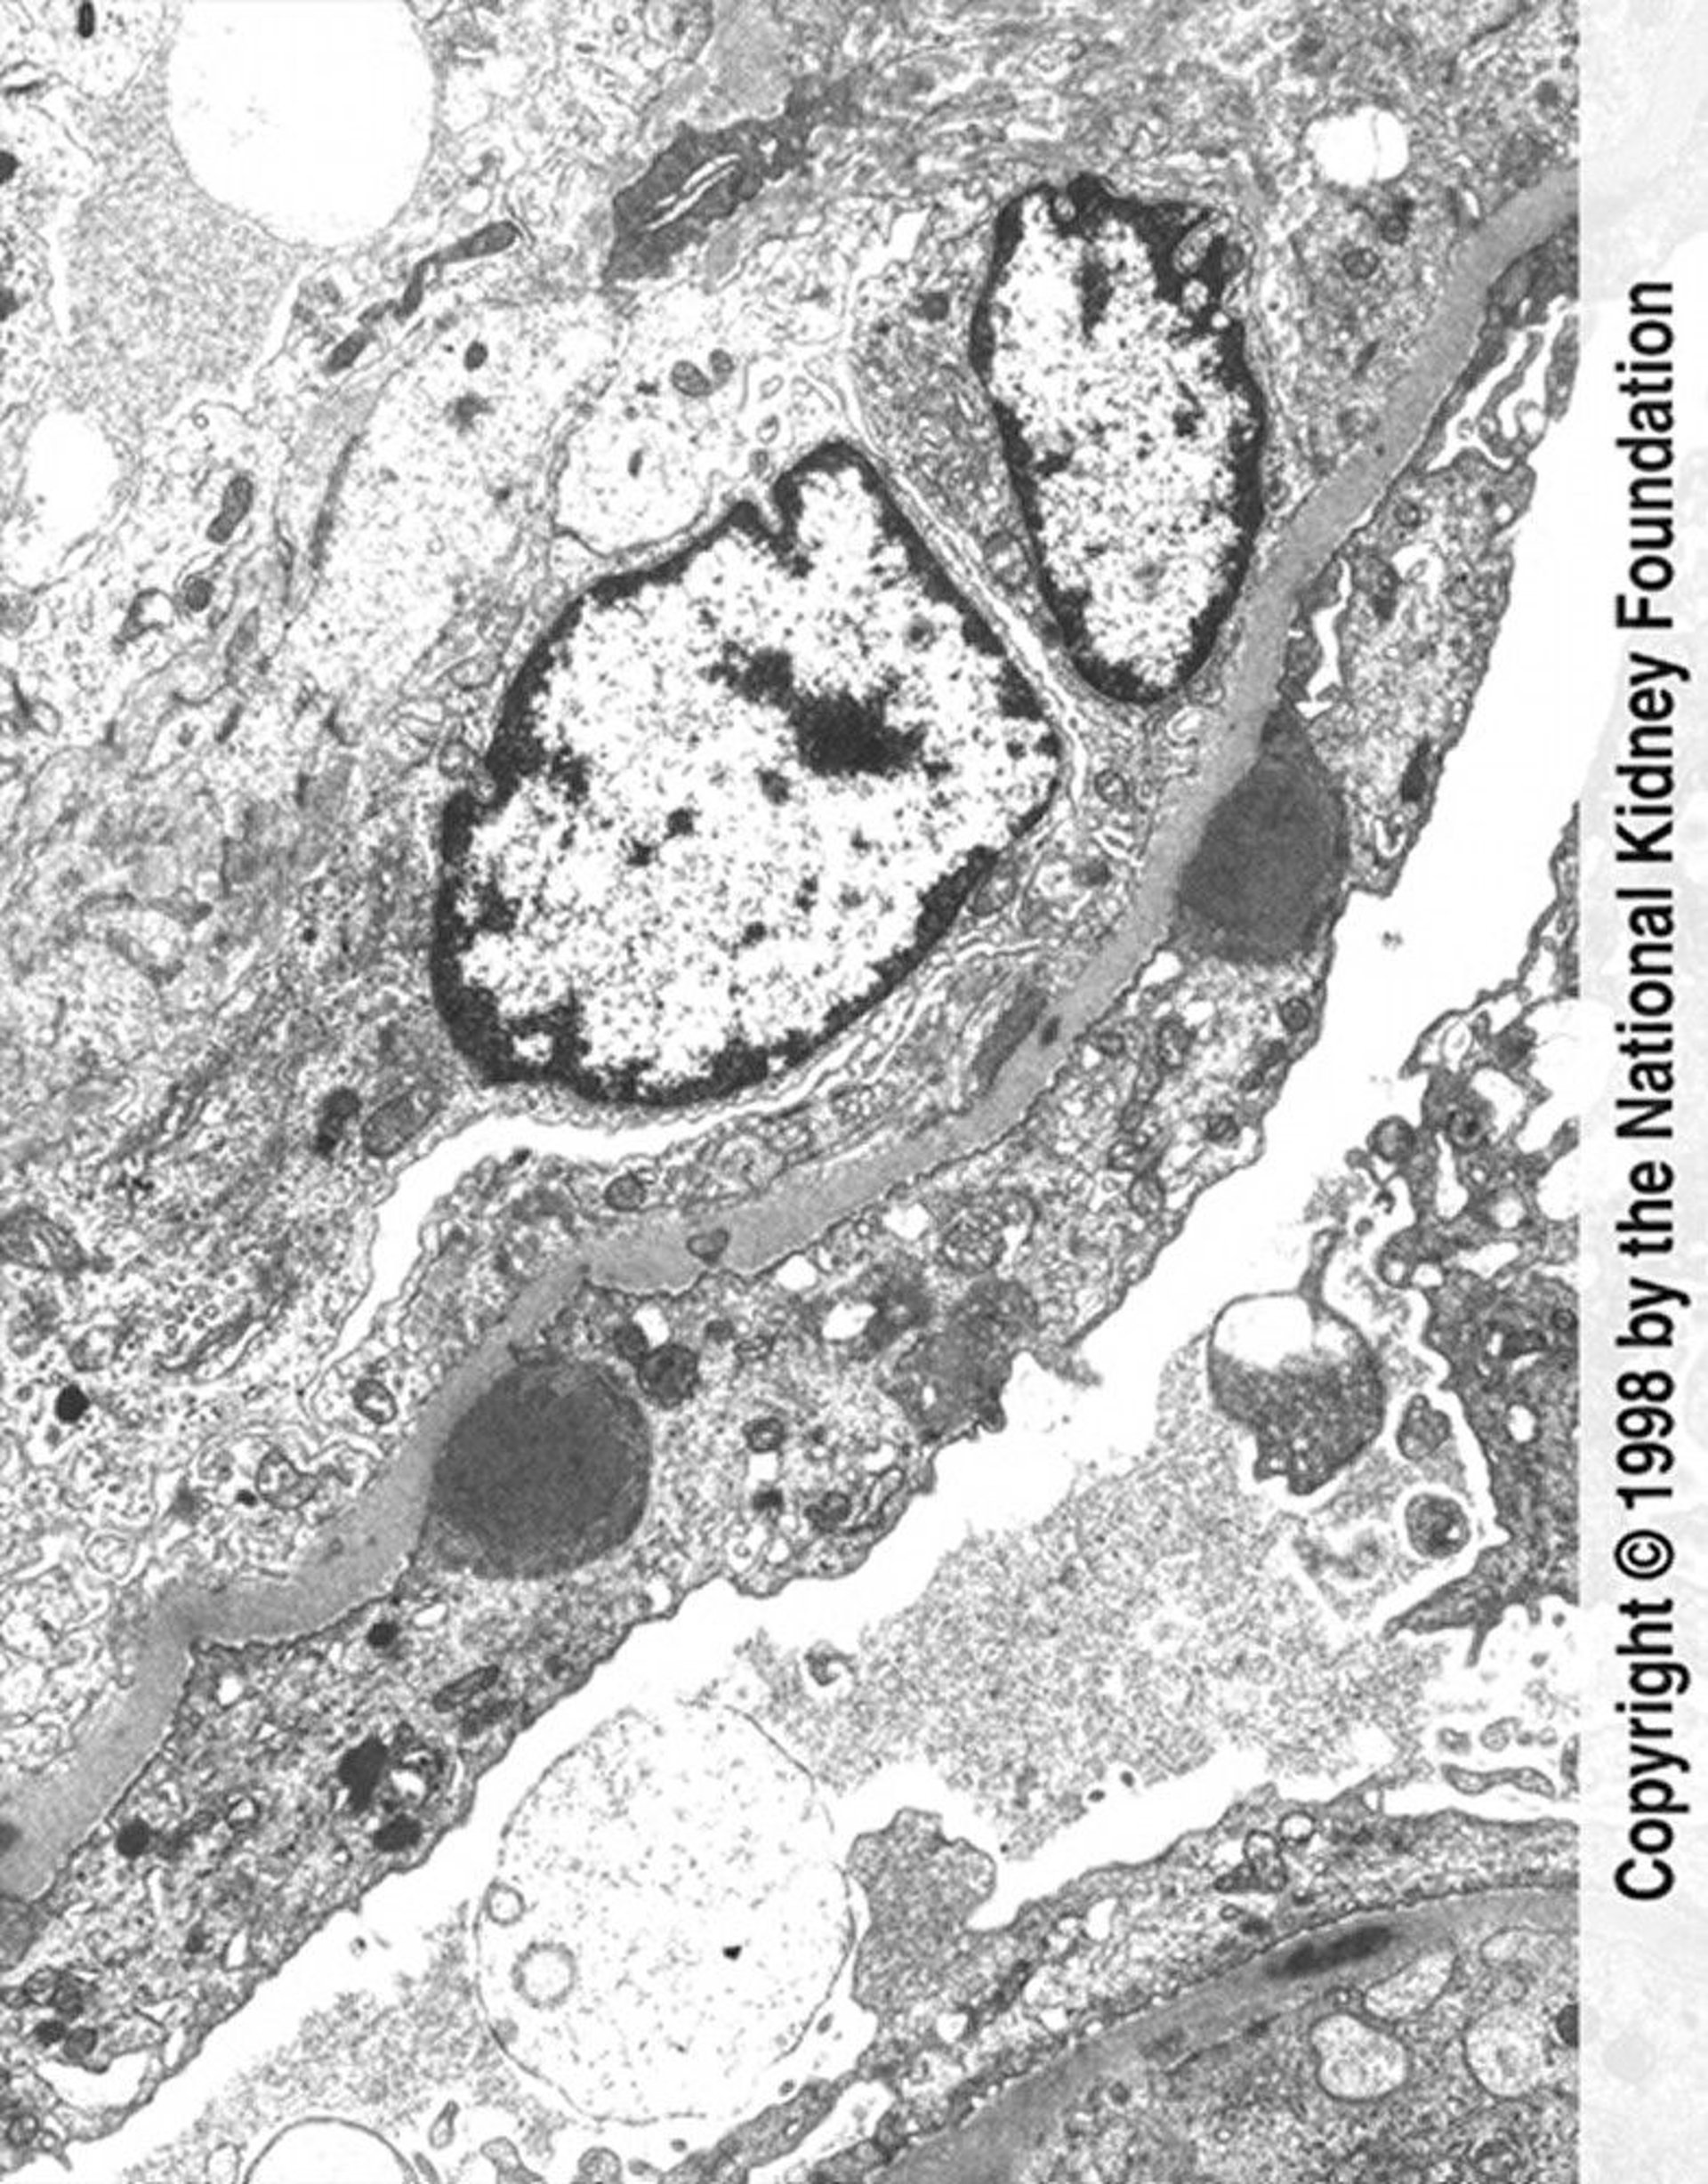

Postinfectious Glomerulonephritis (Immune Complex Deposits)

Hump-shaped immune complex deposits (dark gray) with extensive foot process effacement and endocapillary proliferation are seen on transmission electron micrograph (×11,250).

Image provided by Agnes Fogo, MD, and the American Journal of Kidney Diseases' Atlas of Renal Pathology (see www.ajkd.org).